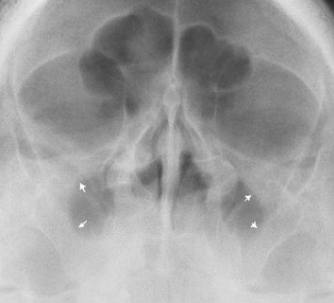

What pathology is pictured here?

nasal polyps from chronic sinusitis